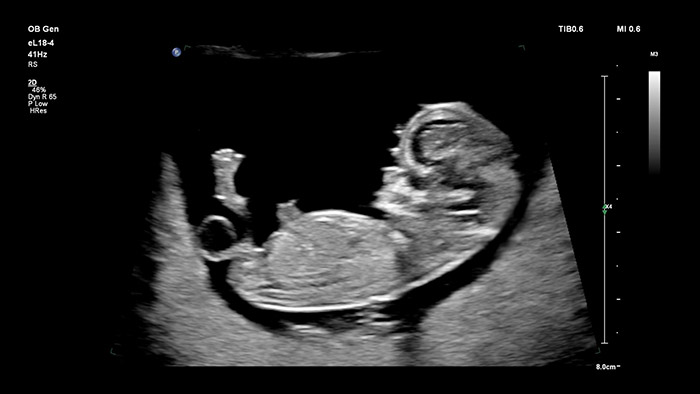

当社のMicroflow Imaging搭載eL18-4トランスジューサは、高解像度2Dイメージングと超高感度の血流検出により、優れた解像度と診断確度が必要不可欠な妊娠初期の総合的な胎児健康評価を可能にします。